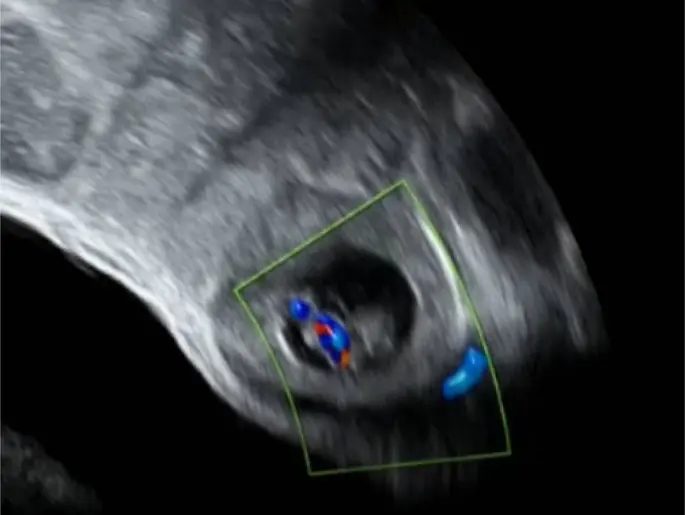

- Ultraschalluntersuchung: Der Ultraschall ermöglicht die Beurteilung des Fötus, der Plazenta und des Gebärmutterhalses.